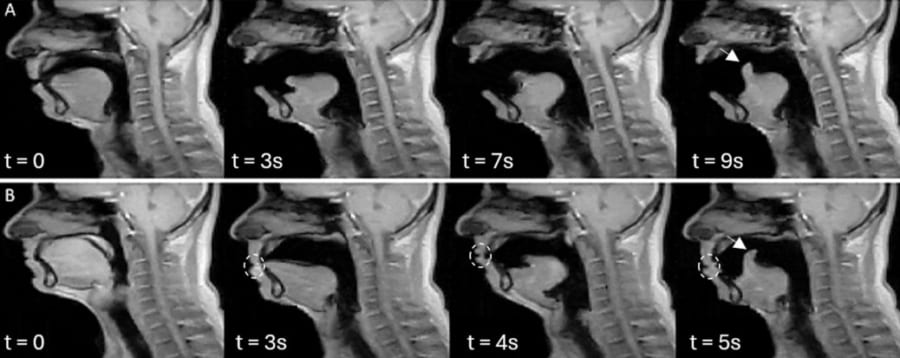

研究チームは、舌の先の少し後ろの部分を目印にして、その点が時間とともにどんな軌跡を描くかを計算しました。

その結果、一人の参加者の中で、別々のタイミングで出たあくび同士を比べると、その軌跡はとてもよく重なり合い、ほぼ同じ線をなぞっていることが分かりました。

数値としても、動きの似かたを表す指標がほとんどの人で高い値を示しており、なかには「ほぼ完全に一致」と言える人もいました。

さらに興味深いのは、「がまんあくび」の場合です。

参加者が口を閉じてあくびをこらえようとしても、舌の奥のほうの動きのパターンは、口を大きく開けた本物のあくびととてもよく似ていました。